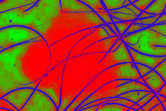

These probability images show the pixel probabilities in graphic format, also taking advantage of the fact that as there are three images, a color image can be built by assigning the to the red channel, to the green channel and to the blue channel. This new image is equivalent to the three probability images and enables the result of the fuzzy classification of pixels to be seen much more clearly in graphic format, all of which is shown in Fig. 3.